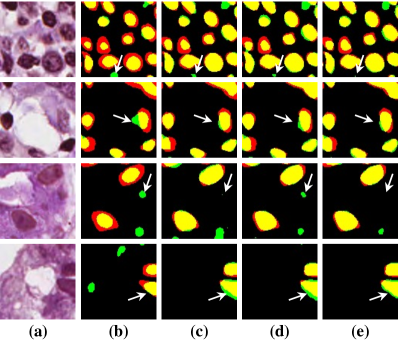

Pathology slides contain abundant phenotypic information, and are widely used to study the manifestations of disease by analyzing cells or tissues under the microscope by pathologists [1]. Nuclei segmentation is a crucial step in pathology image analysis. The shape, size, density, and other indicators of the nucleus are related to the diagnosis and treatment of cancer [2, 3]. Different staining methods are used to increase the contrast between the different structures for their visual examination, where the most commonly used staining method for nuclei analysis is hematoxylin-eosin (H&E) staining, in which nuclei are stained blue-purple by hematoxylin (H-component), and cytoplasm and stromal matrix are stained red-pink by eosin (E-component) [4, 5], as shown in Fig. 1. Besides, with the advent of dedicated scanners, slices can be easily converted to digital pathology images, which are convenient to store on computers for further processing and analysis. Therefore, the wide availability of digital H&E stained pathology images greatly facilitates researchers in developing and validating advanced automatic pathological image analysis methods with nuclei segmentation.

Point annotation can be viewed as the most efficient manner for annotation, gaining increasing attention in cell/nuclei segmentation. Existing methods [23, 24, 25, 26] mainly encode the point annotation into coarse pixel-level labels, such as point distance maps [23], Voronoi labels [24], cluster labels [25], and pseudo edge maps [26]. As shown in Fig. 1, these methods typically inject the shape and texture prior knowledge of nuclei into coarse pixel-level label. For example, the points are assumed to be around the center and the nuclei shapes are nearly convex. Despite drastically reducing the annotation cost and alleviating the data-imbalance problem of point annotation, these methods still suffer from incomplete coarse labels and inaccurate boundary information, as illustrated in Fig. 1. Various methods have been proposed to eliminate the distraction induced by the coarse labels, which can be categorized into two classes: 1) multi-stage optimization to refine the segmentation in a bootstrapping way [23, 27, 24]; 2) adding additional constraints based on the local contrast between nuclei and their surrounding cytoplasm [25, 26]. However, the additional constraints could introduce inaccurate supervision, and a multi-stage learning strategy may suffer from error accumulation (i.e., the global optimum cannot be guaranteed).

In practice, directly using point annotation for the nuclei segmentation could suffer from the data-imbalance problem due to insufficient supervision information. To alleviate this issue, we adopt the Voronoi diagram [24] and the -means clustering method [25] to generate Voronoi label and cluster label, respectively. Specifically, for Voronoi labels, as shown in Fig. 1, the image is divided into convex polygons based on the point annotations with the assumptions that the point labels are at the nuclei centers and nuclear shapes are convex (even though these assumptions are not necessarily valid). For cluster labels, as shown in Fig. 1, we utilize the -means to obtain more supervision information of nuclei boundary and shape as follows. First, we calculate the distance maps from the point labels by performing distance transform between each pair of points. Second, the distance maps are combined with the original H&E stained images to conduct the -means clustering to divide all pixels into clusters: nuclei, background, and ignored area. The clusters that have maximum and minimum overlap with the point annotations are labeled as nuclei and background, respectively. The remaining one is the ignored class. The introduction of an ignored area allows pixels that cannot be easily determined as nuclei or background with certainty not be forced into either class, ensuring that the clustering can assign correct pixel labels as much as possible [27]. Third, several morphological operations are adopted to refine the cluster label, including connected domain labeling, scattered region removing, morphological opening operation, and binary hole filling.

As shown in Fig. 1, although part of the color information is lost in the obtained H-component image, the color contrast between the nuclear and non-nuclear regions is enhanced.

where and denote the Voronoi label and cluster label of nuclei at the -th pixel, respectively; denotes the prediction of the segmentation network with H-component as input; and (i.e., or ) is the set of non-ignored pixels. As illustrated in Fig. 1, the Voronoi label is used to supervise the network to separate overlapping nuclei, while the cluster label could provide coarse shape and boundary information for nuclei segmentation. In the following, we elaborate the co-training strategy to further provide supervision to the ignored area of the coarse cluster labels, denoted with the blue color in Fig. 1.

To investigate the impact of the proposed co-training and colorization methods, we validate the effectiveness of each module on the MoNuSeg dataset. Considering that Voronoi labels provide more shape supervision information than point annotation, we regard the model that jointly uses the point annotation and the Voronoi label as the baseline, and mainly evaluate the improvement of each module upon this baseline in Table III. Model A utilizes only point annotation and Voronoi labels with cross-entropy loss. For a fair comparison with co-training, we employ two separate models which have the same architectures for co-training and average the predictions of the two models in inference. Model B further adopts the cluster label. It can be seen that the cluster loss is beneficial in segmenting overlapping nuclei, improving the from 60.20% to 72.48% and the AJI from 43.01% to 51.77%, which indicates that simply using the point annotation and the derived Voronoi labels cannot provide sufficient supervision for the nuclei segmentation due to the lack of boundary and area information. However, the cluster labels generated by the -means algorithm cannot separate close nuclei which would introduce distraction to the training process, as shown in Fig. 1. To address this challenge, Model C utilizes the co-training strategy that the two models facilitate each other in a bootstrapping way to eliminate the distraction brought by the cluster labels. As expected, co-training brings a consistent improvement in all metrics, including an 1.19% increase to AJI. We believe that co-training compensates for the loss of supervision information in the uncertain regions in the cluster label, and the probability map with EMA by another model provides more precise and robust supervision in the nuclei boundary. Visualization of the segmentation results can be found in Fig. 3, and it can be seen that with the co-training strategy, the model can achieve more accurate results, especially in the nuclei boundary area. Model D involves colorization as a proxy task to implicitly learn to be self-aware of the nuclei boundary. Instead of directly coloring the H-component (Fig. 4(a)) to the H&E map (Fig. 4(d)), we use the segmentation probability map (Fig. 4(b)) as the input of the colorization network, which can help us to boost the segmentation accuracy. The experimental result shows that integrating the colorization tasks could not only improve the by 1.54% and AJI by 3.24%, but also promote Acc by 0.18% without dropping F1 score, proving that the colorization task has a significant guiding effect on nuclei segmentation. In Fig. 4(c), the improvement of colorization in the nuclei boundary area can also be observed. In general, the four modules used in our method have complementary advantages. By minimizing the weighted sum of the four losses, the proposed framework can distinguish between nuclear and non-nuclear to the greatest extent.